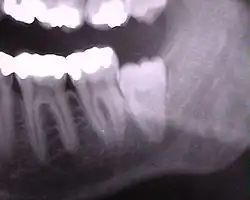

Ретенированный зуб мудрости на рентгеновском снимке

Самым проблемным случаем являются ретенированные зубы мудрости на верхней и нижней челюстях. Зубы мудрости редко растут правильно, чаще они пытаются прорезаться под углом или горизонтально по отношении к остальному зубному ряду. Это приводит к давлению на соседние зубы и их разрушению со временем. Данную патологию можно диагностировать на 3D-томографии — она ясно показывает расположение ретенированных зубов мудрости.